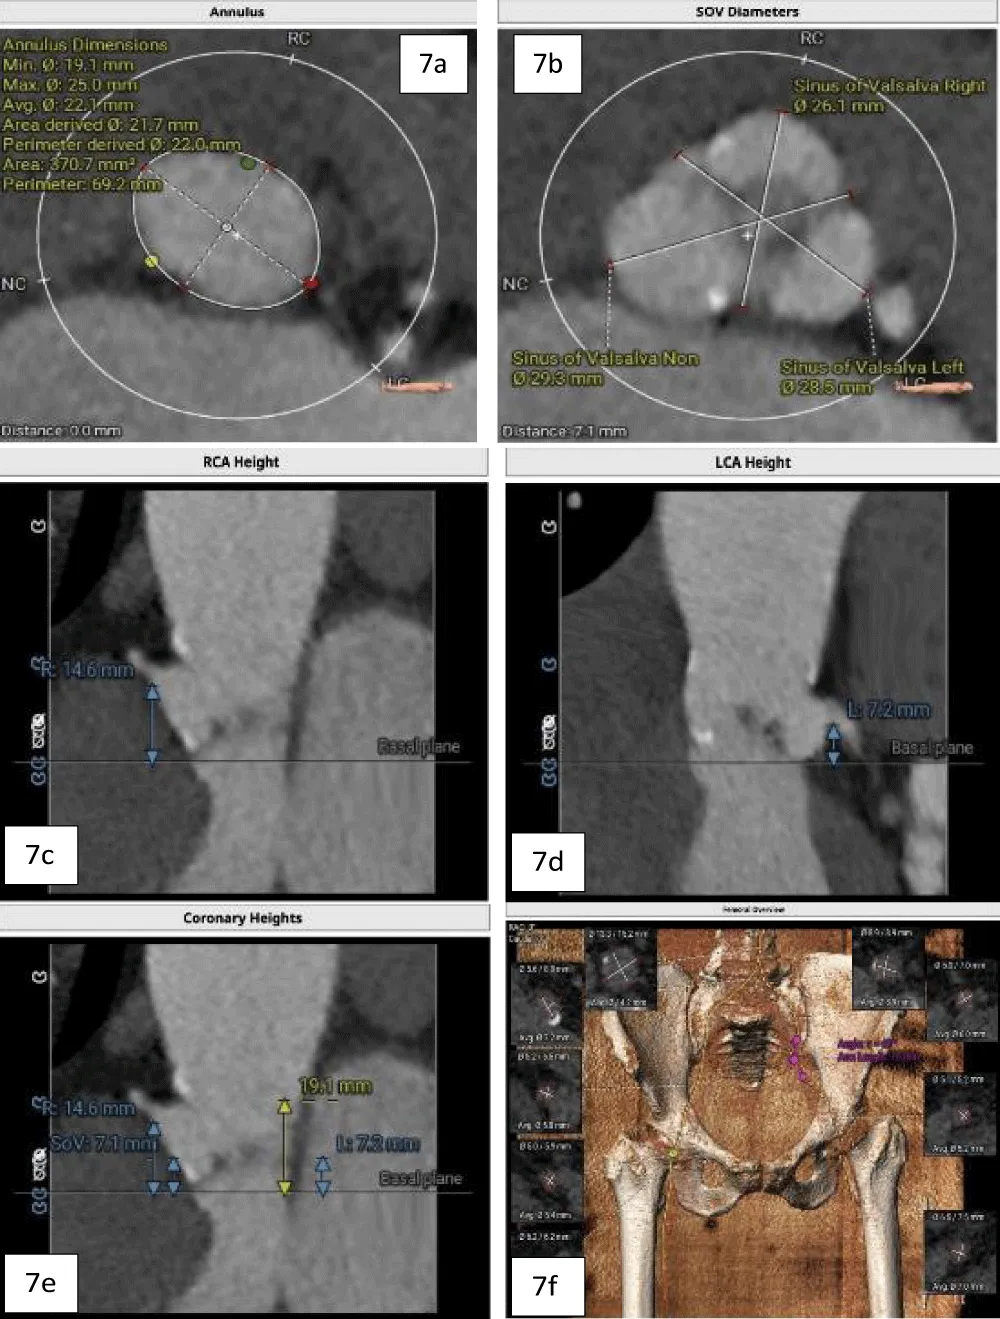

The patient’s past surgical notes were traced, which revealed that the initial AV replacement was performed using a 21 mm CROWN PRT™ stented bioprosthetic valve (LivaNova PLC, London, United Kingdom). Since the patient had high EuroSCORE II and STS scores, the Heart Team selected TAVI. Following the pre-TAVI screening, her coronary angiogram revealed non-obstructive lesions in the left anterior descending (LAD) artery. The 2-D contrast-enhanced CT and aortography revealed an average aortic annulus diameter of 21.9 mm, annular area of 381.9 mm2, and annulus perimeter of 69.4 mm, as seen in Figure 2a. The sinus of Valsalva (SOV) diameters of the left, right, and non-coronary cusps were 27.4 mm, 28 mm, and 31.6 mm, respectively (Figure 2b). However, the right and left coronary ostial (LCO) heights were 10 mm and 6.8 mm, respectively, both being abnormally low including the critically short LCO that was well visualized on CT (Figure 2c,2d). The SOV height was 9.3 mm and the height of the sino-tubular junction (STJ) was 13.1 mm (Figure 2e), while the average diameter of the STJ was 28.2 mm. In terms of access, both the femoral and iliac arteries had acceptable diameters on both sides without severe calcification showing suitability for a transfemoral approach (Figure 2f). On 2D-CT, the predicted VTC distance was 6.7 mm for the right coronary ostia (RCO) and 4.1 mm for the LCO, if a 21.5 mm Myval THV was used (Figure 3). The 21.5 mm BE Myval (Meril Life Sciences Pvt. Ltd., Vapi, India) was selected to be deployed under rapid pacing.

Download Image

Figure 3: Showing the VTC reconstructed on 2D-CT (left: 6.7 mm; right: 4.1 mm) with the implantation of the selected 21.5 mm Myval THV.